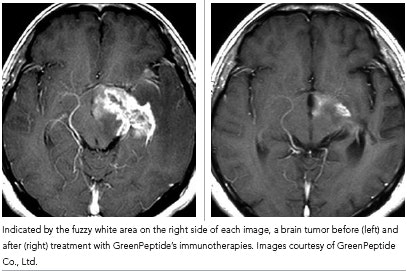

Clinical studies on 400 cancer patients found that a select group of the peptides was very effective in treating some cancers, and that the same set of peptides could be used to treat different cancers. The most dramatic results were observed in the treatment of malignant brain tumors, where the peptides were observed to cause dramatic shrinkage within six months (see photo below). Results were also evident in treating hormone-refractory prostate cancer, where treatments appeared to stop bone metastasis in some patients. Hepatitis C therapies are at the translational research phase at the university right now.